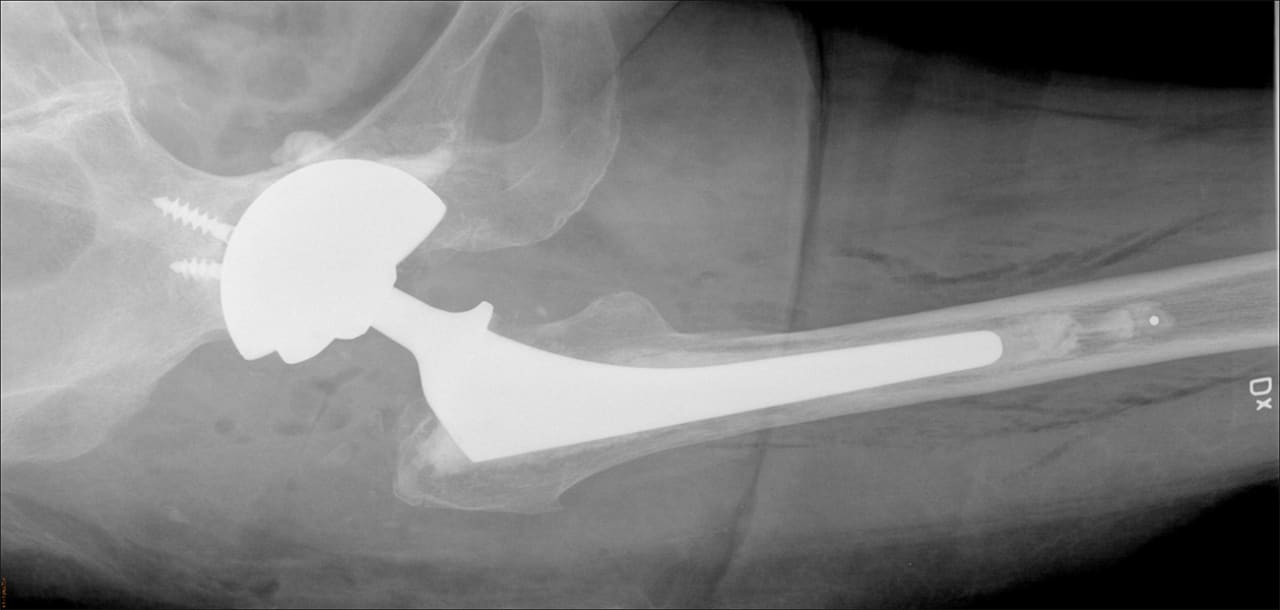

Vid omoperation av höftproteser kan risken för instabilitet minska med en metod där man cementerar fast dubbelskålar i en större metallskål, CMC-metoden.

– Vid omoperation av lösa höftproteser använder man sig ofta av stora skålar av metall. Detta kan leda till att höftprotesen hoppar ur led vilket är mycket smärtsamt och ofta kräver ytterligare operationer. En ny metod som utvecklats här på Akademiska sjukhuset innebär att man cementerar fast dubbelskålar i en större metallskål, vilket minskar denna risk, säger Anders Brüggemann, ST-läkare i ortopedi, Akademiska sjukhuset, som lett studien som publicerats i den vetenskapliga tidskriften Acta Orthopaedica.

Studien baseras på data från det loka höftprotesregistret i Uppsala och omfattade patienter som genomgick byte av höftledsprotes mellan 2008 och 2016. Totalt följde man upp 184 höftledsbyten på män och kvinnor i åldern 35-88 år (genomsnittsåldern var 67 år). Forskarna jämförde utfallet av två metoder, en där man cementerat fast dubbelskålar, så kallad DMCs, i en större metallskål, och en där man använde en enklare plastskål insatt i metallskålen.

– Endast hos en patient som opererats med DMC-metoden hade höftprotesen hoppat ur led. I kontrollgruppen, som opererats med den konventionella metoden, hade däremot 14 patienter sådana komplikationer, konstaterar Anders Brüggemann. Våra resultat talar för att patienter som löper hög risk att höftprotesen hoppar ur led bör erbjudas denna metod i samband med omoperation.